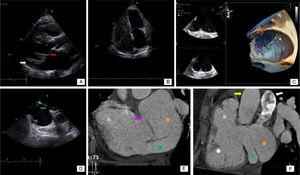

Besides her known conditions, the TTE showed a dilated coronary sinus (CS) and right ventricle that was not proportional to the MR. Transesophageal echocardiography (TEE) revealed prolapse of the mitral valve anterior leaflet (Figure 1A). The CS was markedly dilated, with no opacification after saline injection (Figure 1B). There was echo dropout in the left atrial wall and communication with the CS, raising the suspicion of unroofed CS (URCS) atrial septal defect (ASD). Three-dimensional echocardiography showed absence of the CS wall (Figure 1C) and the already known PFO (Figure 1D). Coronary computed tomography angiography (CCTA) confirmed the diagnosis of URCS (Figure 1E and F). Right catheterization showed a cardiac index of 11.47 l/min/m2, pulmonary artery pressure of 47 mmHg, and significant left-to-right shunt (Qp/Qs 2.2). The patient underwent mitral valve replacement and ASD closure. The PFO was left open. Postoperative course was uneventful and the patient was still asymptomatic at one year.

(A) Transthoracic echocardiography (TTE), parasternal long-axis view, showing the mitral valve (red arrow) and the enlarged coronary sinus (white arrow); (B) TTE, 4-chamber view, after injection of saline, without significant opacification; (C) three-dimensional echocardiography showing the coronary sinus (red dot) and left atrium (yellow dot) and revealing the absence of the coronary sinus wall; (D) transesophageal echocardiography showing the patent foramen ovale (green arrow); (E) coronary computed tomography angiography (CCTA) showing the right atrium (blue dot), left atrium (orange dot), the enlarged CS (green dot) with missing roof, communicating directly with the left atrium, and a communication between the right and left atria (purple arrow); (F) CCTA showing the right atrium (blue dot), right ventricle (white dot), left atrium (orange dot) and enlarged coronary sinus (green dot). The aorta (yellow arrow) and pulmonary artery (white arrow) can also be seen.